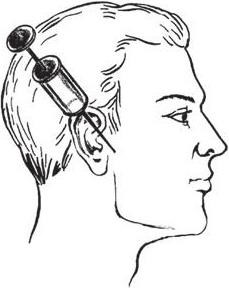

При выполнении анестезии подскуловым доступом (по Берше – Дубову) иглу вкалывают в кожу перпендикулярно к ее поверхности под нижним краем скуловой дуги на 2 см кпереди от основания козелка ушной раковины. Продвинув ее на глубину 3 – 3,5 см и достигнув тем самым внутренней поверхности наружной крыловидной мышцы, вводят 2 мл анестезирующего раствора. В результате через 8 – 10 мин происходит блокада нижнего альвеолярного, щечного и язычного нервов. Несколько раньше частично или полностью устраняется контрактура нижней челюсти (рис. 1.7).

Рис. 1.7. Обезболивание нижнеальвеолярного, щечного и язычного нервов (по Берше Дубову)